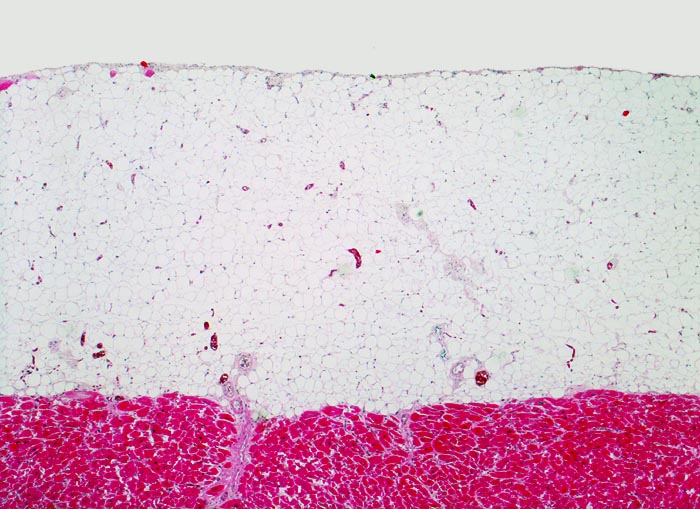

Normales Epikard

Perikard

Das einschichtige Mesothel ist in dieser Vergrösserung nicht erkennbar. Auf eine schmale subepitheliale Stromaschicht folgt das epikardiale Fettgewebe, welches beim individuellen Patienten sehr unterschiedlich dick sein kann. Unten im Bild das Myokard.